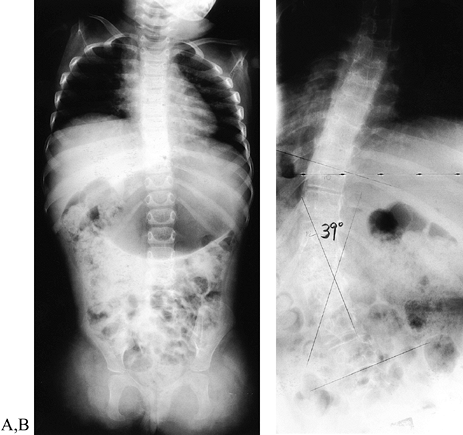

anomaly, but children with amelia (failure of formation at the shoulder

level) have a high incidence of scoliosis (138) (Fig. 165.23). Cognition and developmental milestones are usually normal, except that the child with a very short arm may not crawl.

Figure 165.23. Girl with transverse failure of formation of upper (and lower) extremities. A: Radiograph of the spine (the child was 2 years of age). B: Radiograph of the spine (12 years of age) with 39° scoliosis.